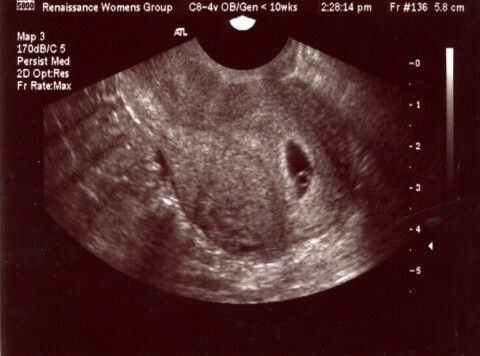

Inutile ! la présence d’une vésicule vitelline et d’un sac gestationnel signe la présence d’une grossesse et son caractère intra-utérin

Votre échographie retrouve cette image :

La patiente a maintenant quelques métrorragies minimes.